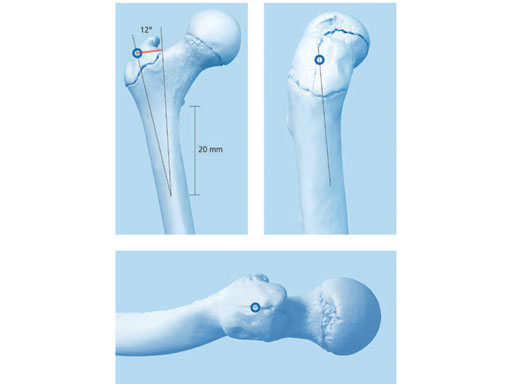

Conventional antegrade nailing of the femur in this age group is a concern because of the possibility of avascular necrosis of the femoral head. This is rare but devastating. The ALFN has a lateral trochanteric entry point and a double curved configuration (double bend in two planes and additional tip bend) to avoid compromising the ascending branch of the medial femoral circumflex artery near the piriformis fossa. The recommended entry site is on the bare aspect of the greater trochanter 1520 mm distal to the tip of the greater trochanter and forms an angle of 1214 lateral to the greater trochanter, as measured from the lateral entry point to a point 20 mm distal to the lesser trochanter (Fig 2).

The adolescent lateral entry femoral nail is part of the expert nail family, therefore most instrumentation is identical, except for a new insertion handle aiming arm (Fig 3), 13 mm drill sleeve, and 5.0 mm recon screw drill bit. The ease of finding the entry point is maximized if the greater trochanter is positioned in profile to the beam of the C-arm. This can be done in either supine or lateral decubitus position.